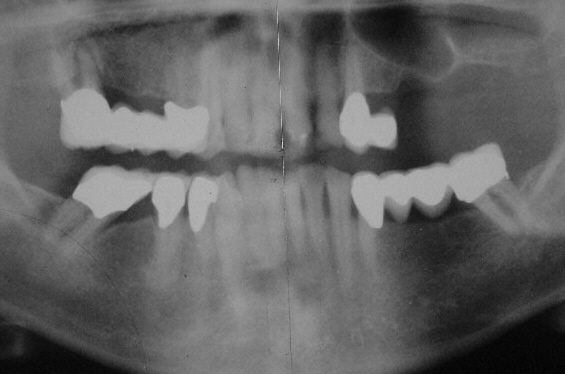

Ausgangs-OPT 1992 (Klick!)

Sekundär waren die Zähne über individuell gefräste RSS-Geschiebe verblockt. Distal am 33 befindet sich ein Prezi-Vertix-Geschiebe. Wenn wir uns auch bemühen, so können wir uns beim besten Willen nicht erinnern, warum wir damals den Zahn 14 nicht mit einbezogen und ebenfalls über ein Prezi-Vertix-Geschiebe an die Prothese angebunden haben. Wir hatten ihn - mit welcher heute nicht mehr nachvollziehbaren Begründung auch immer- vielmehr über ein Teleskop angebunden. Im Nachhinein betrachtet stellt sich das als Planungsfehler dar. In 2001 musste 14 nach unfallmäßiger sehr tiefer Kronenfraktur (Bruxismus) entfernt werden, wodurch es zu einer starken Instabilität der Prothese mit der Folge rezidivierender Frakturen der Sekundärteile der RSS-Geschiebe kam. Um die Versorgung zu retten haben wir Anfang 2002 ein Einzelimplantat in Regio 15 gesetzt und es wegen schlechter Knochenqualität 6 Monate einheilen lassen.